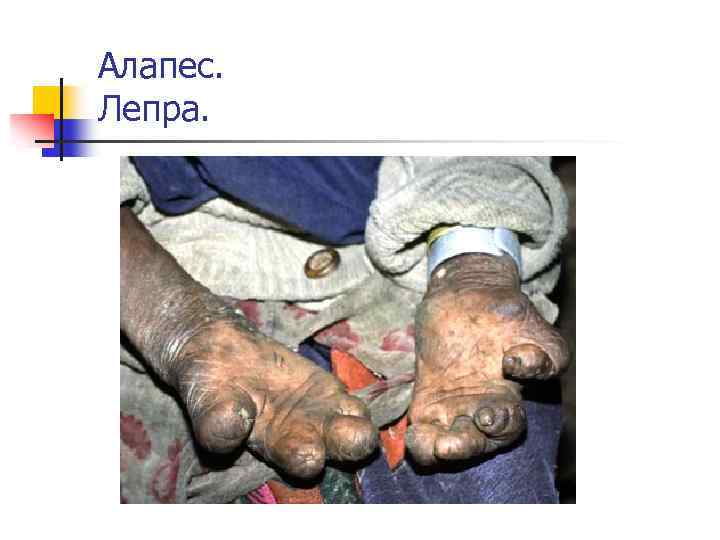

Алапес. Саусақтар мутиляциясы. Лепра. Мутиляция кисти.